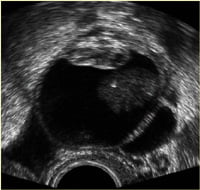

Dermoid kistin ultrasonografik görüntüsü